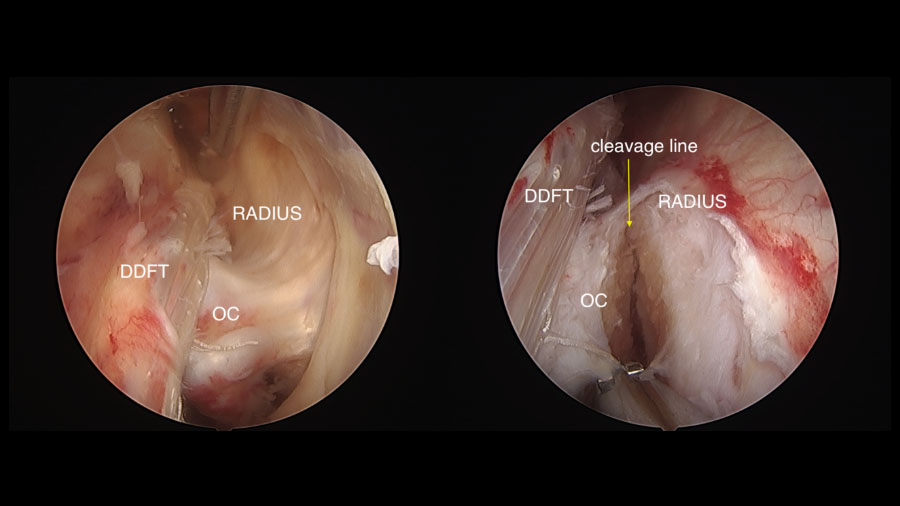

A standard tenoscopic approach is made to the carpal sheath and an incision is made in the thickened synovium overlying the base of the boy spike. An osteotome is then seated parallel to the caudal radius and a mallet used to section the osteochondroma or spike in a lateral to medial direction. The bone is usually left attached by medial soft tissues and can be safely removed with rongeurs.

If large it can be sectioned using a mechanical burr or left in situ to be removed after tendon debridement via an enlarged portal. Enlarging a portal prior to completing tendon debridement with an oscillating mechanical resector results in loss of fluid pressure, extensive bleeding and an inability to complete the procedure.

The DDFT tear (and any damage to SDFT or RH-DDFT) is debrided with the resector and the sheath lavaged before routine skin closure and bandaging.